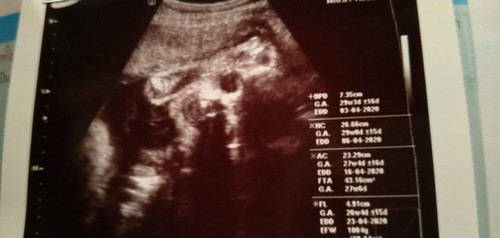

28w

แม่ไปบ้านอื่นน้องเอาหัวลงตอนกี่สัปดาห์คะ แม่บ้านนี้28สัปดาห์น้องเอาหัวลงแล้วจ้าา